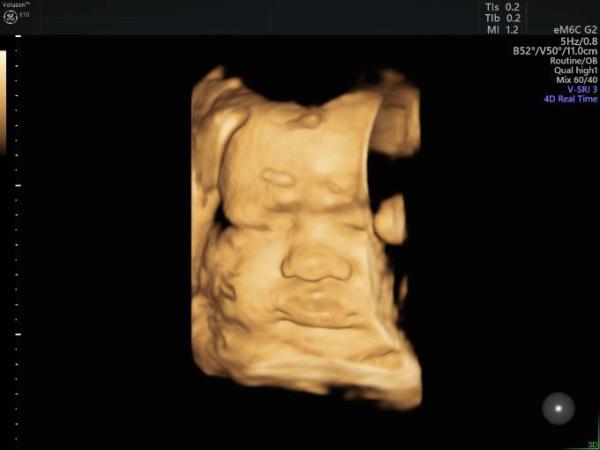

Endlich, in der 38SSW zeigt sich unser Überraschungsei! Heute bekamen wir endlich ein Foto vom Gesicht. Es hat sich die gesamte Schwangerschaft über immer weggedreht, lag mit dem Rücken zu uns etc. Aber heute durfte ich mir diese süße Zuckerschnute anschauen! Mir kamen direkt ein paar Tränchen vor Freude! Leider liegt es immer noch in BEL und der Po hat sich auch schon richtig in mein Becken festgesetzt. Da ich bereits einen Kaiserschnitt hatte, gibt es nun leider einen geplanten Kaiserschnitt bei 39+5, am 24.01.

Bild zu Schockverliebt - Forum für Januar - Mamis